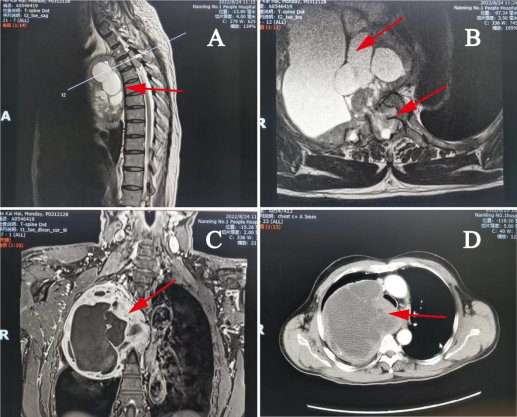

4. 脊柱肿瘤手术

图注:上胸椎巨大肿瘤,联合心胸外科行肿瘤切除术,术后患者下肢肌力由术前2级恢复到4级。